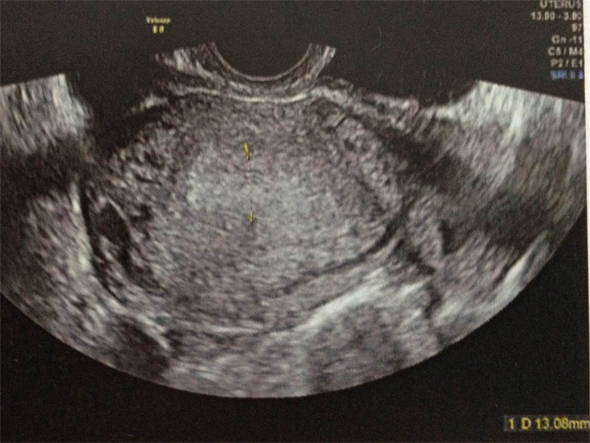

On évoque, en priorité les diagnostics d’urgence ( = diagnostics GRAVES ), donc GEU , la salpingite et la torsion d’annexe.

La salpingite est un diagnostic grave et urgent également (risque de sepsis, sepssis sévère…)

Ici le tableau clinique associant douleur pelvienne d’apparition progressive, peu intense, latéralisées à des pertes marrons et une fébricule à 37,7°C est évocateur.